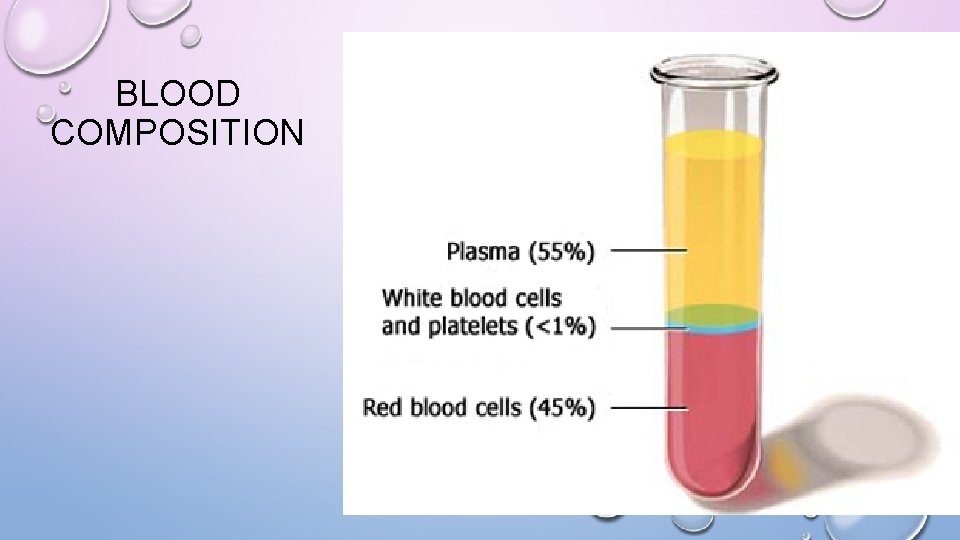

BLOOD COMPOSITION

INTRO. TO CIRCULATORY SYSTEM • HUMANS HAVE A CLOSED CIRCULATORY SYSTEM • BLOOD IS CONFINED TO VESSELS • 5 LITERS IN 1 HUMAN = 7 -8% OF YOUR WEIGHT • 3 DROPS OF BLOOD IS 1 BILLION RBC • 600 RBC = 40 PLATELETS AND 1 WBC

BLOOD COMPONENTS 1. PLASMA- LIQUID CONTAINS: • CLOTTING FACTORS • HORMONES • ANTIBODIES • GASES, WASTE, NUTRIENTS

BLOOD COMPONENTS 2. ERYTHROCYTES- AKA RED BLOOD CELL • CARRY HEMOGLOBIN, • NO NUCLEUS, 120 DAY LIFE, • CANNOT REPAIR THEMSELVES, ERYTHROPOIESIS

3. LEUKOCYTES- WHITE BLOOD CELLS FORMED IN BONE MARROW, FIGHT INFECTION 5 TYPES • NEUTROPHIL - 58%; MAIN DEFENSE, PHAGOCYTOSIS • LYMPHOCYTE- 30%; B AND T CELLS, IMMUNITY, RECOGNITION • EOSINOPHIL- 2%; PARASITE/ALLERGIES • GRANULOCYTE- DIGESTIVE ENZYME

3. LEUKOCYTES- WBC 5 TYPES (CONTINUED) • BASOPHIL- 1%, ALLERGIES? ? ? UNKNOWN • GRANULOCYTE • MONOCYTE- 4% CREEPERS • GO AND LIVE IN TISSUES AND COME OUT WHEN NEEDED • GRANULOCYTE

CLOT IT UP! • 4. THROMBOCYTES- PLATELETS • CLOT BLOOD BY STICKING TOGETHER AND SECRETING PROTEIN CALLED FIBRIN • SUPER SMALL